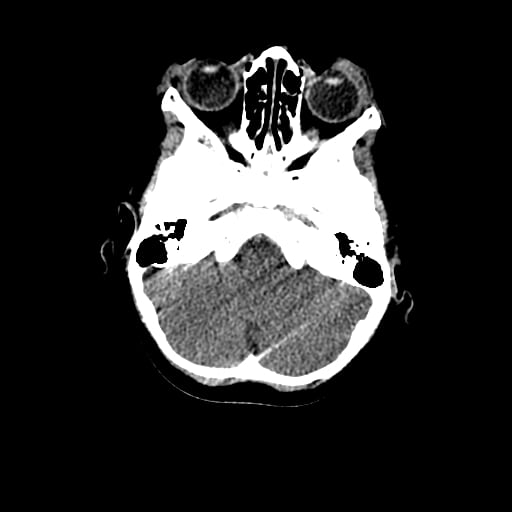

Age: 1

Sex: Male

Indication: Fall